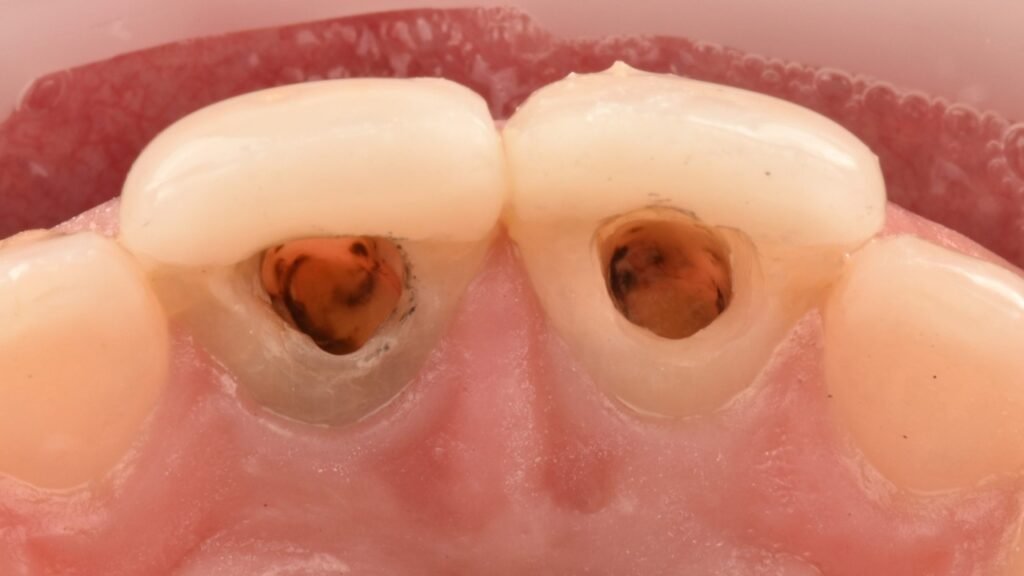

La endodoncia con microscopio es un tratamiento de alta precisión indicado cuando la caries o un traumatismo han alcanzado la pulpa dental. Gracias al uso de magnificación, podemos limpiar y sellar los conductos con una exactitud superior.

Este tratamiento permite eliminar el dolor y salvar el diente, evitando su extracción.

El tratamiento de endodoncia dental se aplica cuando es necesario para salvar un diente una vez la caries ha llegado al nervio. De este modo se eliminan los microorganismos y la infección dentaria. Siendo el único procedimiento definitivo capaz de eliminar el dolor agudo de forma definitiva y lo más conservador para la pieza dental.